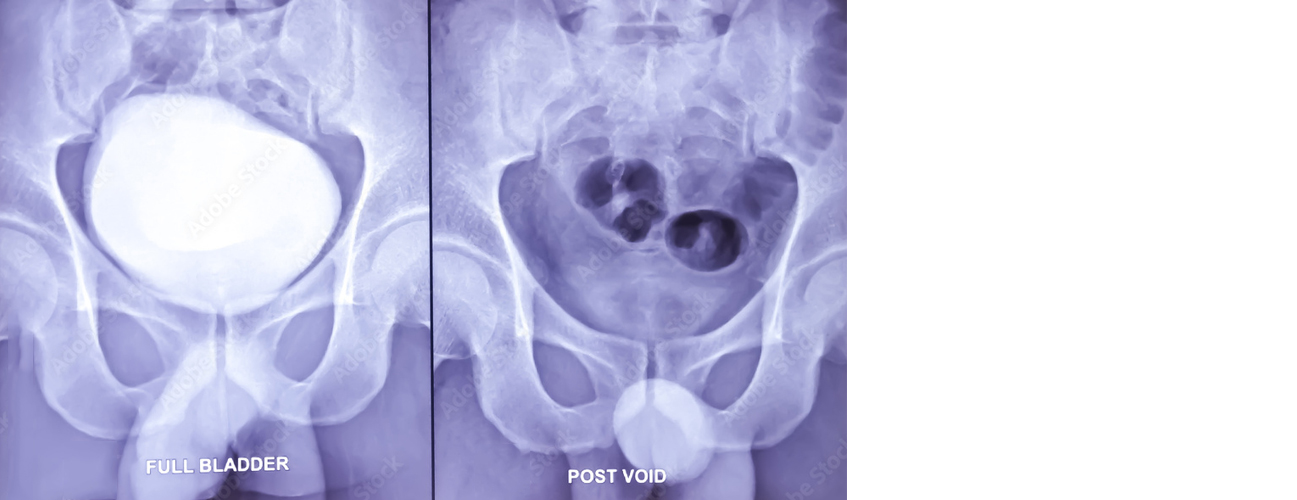

MCU (Micturating Cystourethrogram): This procedure involves taking a series of X-ray images while the patient urinates. A contrast dye is inserted into the bladder through a catheter, and as the patient voids, X-ray images capture the flow of urine from the bladder through the urethra. MCU helps detect abnormalities such as vesicoureteral reflux (where urine flows backward from the bladder into the ureters), bladder or urethral abnormalities, strictures, or obstructions. It's commonly used in children with recurrent UTIs or congenital abnormalities.